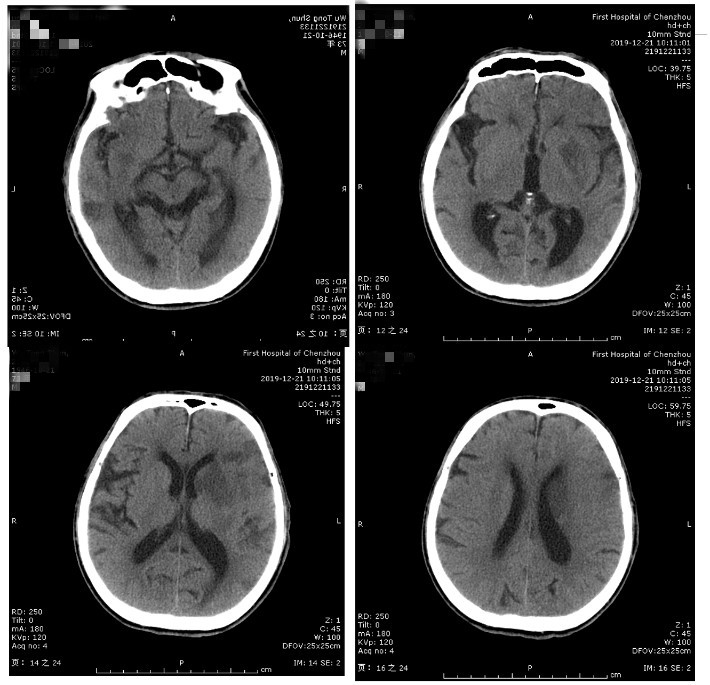

术后即刻查体:神志嗜睡,完全性失语,不全性右侧凝视,右侧鼻唇沟浅,右侧上肢肌力1级,下肢肌力2级,NIHSS评分18分。

术后5天查体:神志清楚,运动性失语,右侧鼻唇沟浅,右侧肢体上肢肌力3级、下肢4级,NIHSS评分8分。